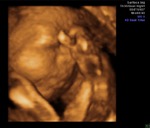

Пузатые новости, УЗИ 29 недель!

Обещают не худенького малыша. Он щекастый и с большим пузиком!

Сосал свою ножку! Потом руку приложил ко лбу, как будто задумался о чем-то очень серьезном!

На первом фото он ручку поднес к лицу. На втором - просто лицо.